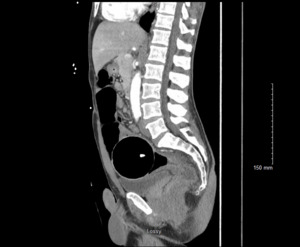

An adult male presented to the Emergency Department with a retained rectal object. On presentation, the patient was clinically stable, though he reported feeling constipated and bloated after four days with the object in situ. A CT abdomen and pelvis with intravenous contrast was performed which demonstrated a 8.2 cm spherical foreign body in the distal sigmoid colon with thickening of the distal sigmoid colon and rectum. There was no evidence to suggest perforation. (Figures 1-2) The retained object was a sphere made of hard plastic with a light inside. A chain attached to the sphere had broken off–not allowing the patient to remove the object himself. Initial attempts made to evacuate the object in the emergency department included the use of an obstetric vacuum delivery system; however, the patient was unable to tolerate these attempts. He was then taken to the operating room for removal under general anesthesia. In the dorsal lithotomy position, the sphere was able to be palpated. Given the hard material of the object, it was not able to be grasped or penetrated with Kocher clamps or myoma screws. An obstetrical vacuum was able to guide the object caudally into the rectum, but the vacuum was not able to fully extract the object. Ultimately, an obstetrician-gynecologist applied Tucker McClane obstetric forceps around the object and was able to successfully deliver the sphere. A general surgeon subsequently performed endoscopy to confirm there were no rectal or sphincter lacerations. The patient was able to be discharged home the same day.